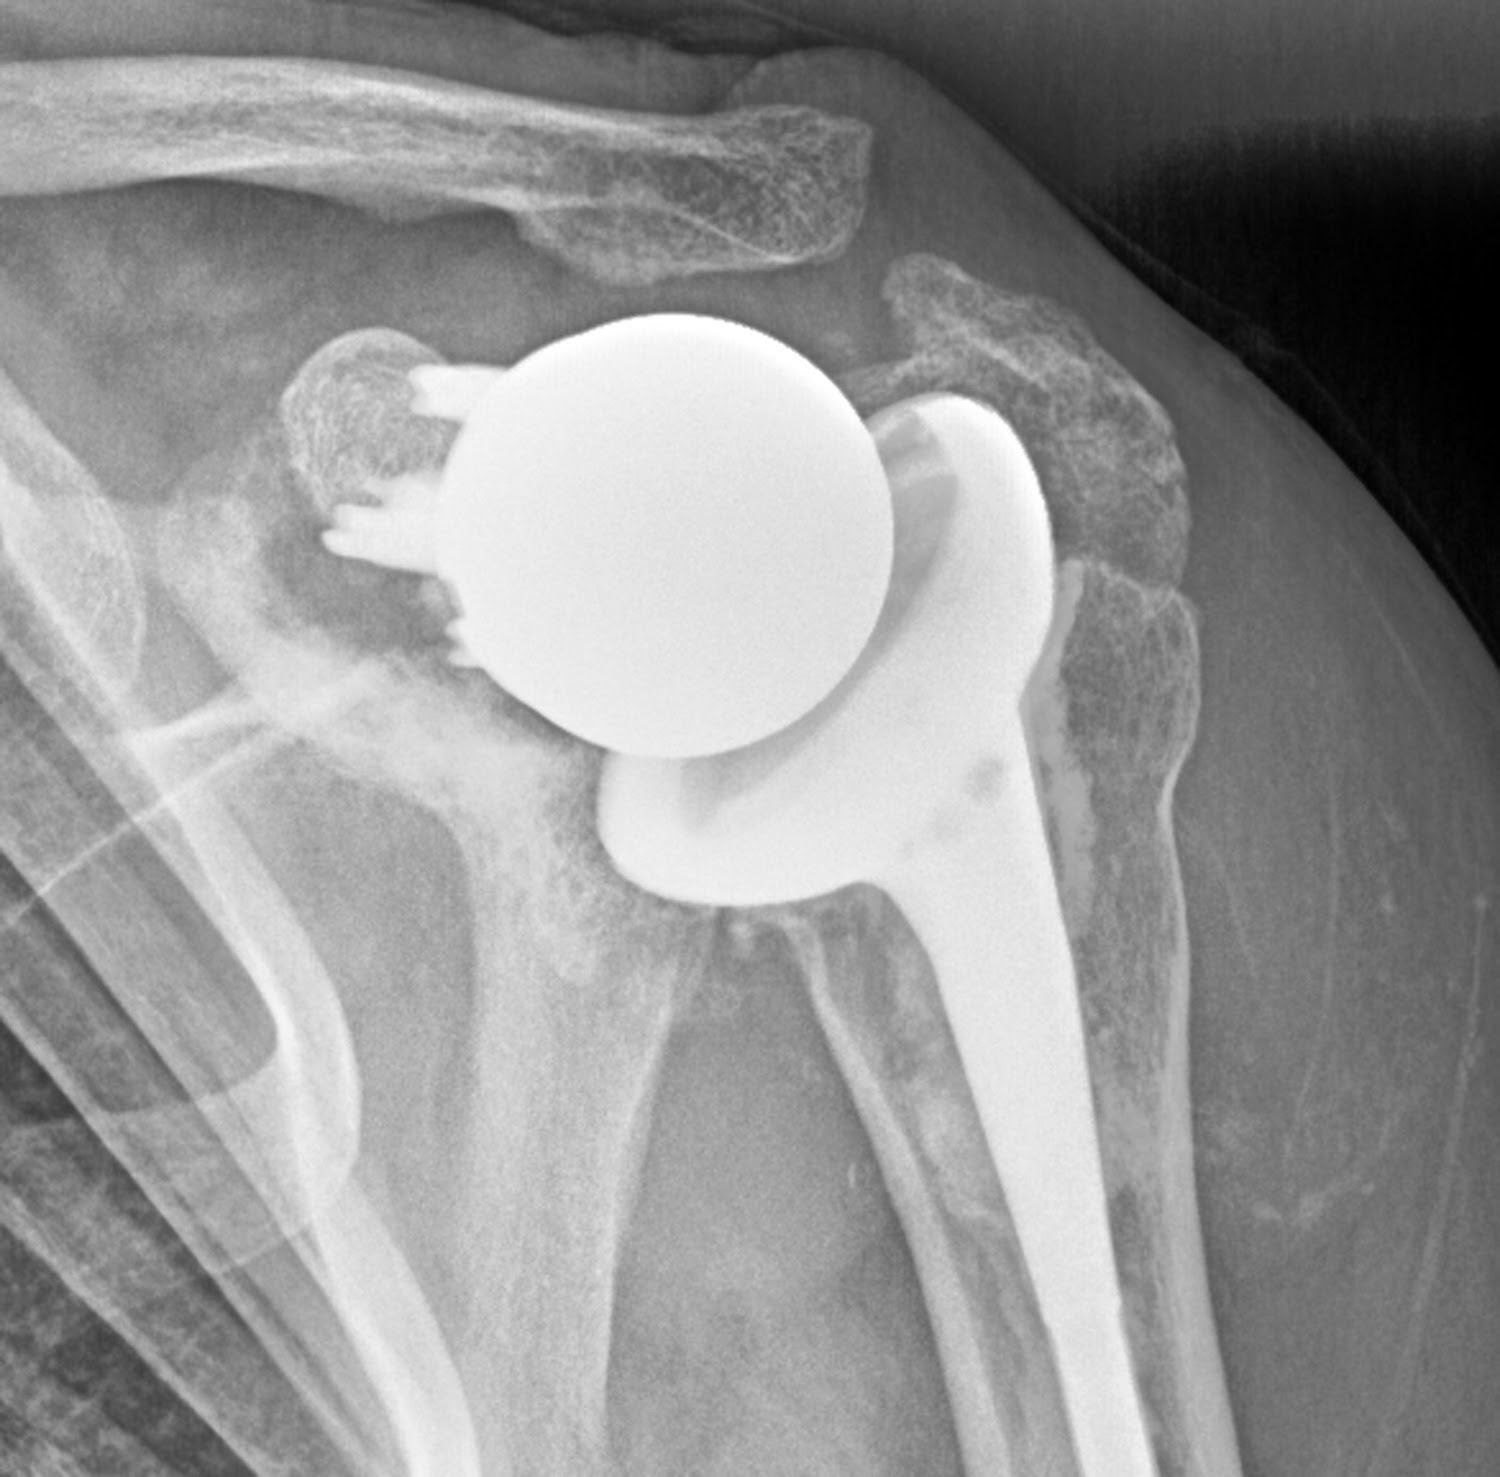

Revolutionize Reverse Shoulder Replacement with the INHANCE™ Shoulder System Johnson & Johnson

What is Right Reverse Total Shoulder Arthroplasty shoulder clinic Hyderabad Why Is Reverse Shoulder Replacement So Painful the three most common problems with reverse shoulder replacements are neurologic injury, bone fracture around the. However, a small subset of patients could. — because of the method used and the positioning of the new artificial shoulder joint, most patients report less. here are five things you should readily expect following a reverse shoulder replacement surgery. A. Why Is Reverse Shoulder Replacement So Painful.